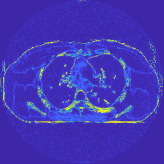

Fig. 7 studies the influence of regularization parameters and on PWLS-ST-. Given a fixed hard-shrinkage parameter , a larger value better removes noise (or unwanted artifacts), but too large can oversmooth reconstructed images; compare Fig. 7(a) and Fig. 7(b). Given a fixed regularization parameter , a larger value leads to lower sparsity in sparse codes and achieves better noise reduction, but too large can remove some edges (e.g., in bone regions); compare Fig. 7(c) and Fig. 7(d). In particular, Fig. S.8 in the supplement shows that once the value is properly chosen, PWLS-ST- is robust to a wide range of values.